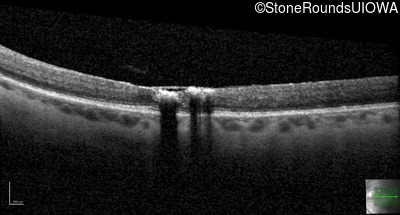

Age at visit: 47 years

OD OS

This 47 year old woman began wearing glasses at age 5 and had cataract surgery at age 32. At that time her doctor noticed a retinal abnormality.